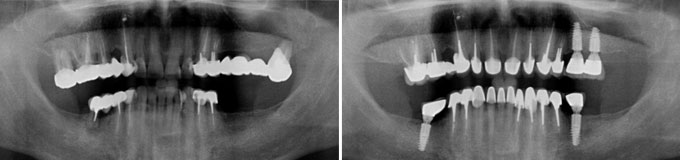

Une situation de pertes dentaires multiples et infections sous des racines naturelles.

Final : traitements de racines effectués et dents manquantes remplacées.

J’ai de vieux bridges à refaire et je veux autre chose.

Solution : on les remplace par la mise en place de plusieurs implants

Un grand bridge supérieur à refaire, le patient veut des dents individuelles.